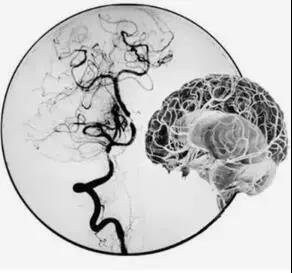

吴主任首先完善脑血管造影(DSA)检查,并详细结合CT、核磁共振检查以及患者右边大脑出现的如虫蛀般大大小小梗塞灶,最终判断疾病“元凶”是罕见的“烟雾病”。

“正是因为重要血管无法正常工作,导致患者脑部‘催生’出很多新生异常血管,这些血管很细很密,在血管造影下,就像烟雾一般,因此被称为烟雾病。”吴主任介绍。

DSA脑血管造影发现患者右侧一根主干颈内动脉完全闭塞、对侧的颈内动脉也出现狭窄,这意味着供应脑部血液的四根主要血管,两根都有问题。此时的李女士右边大脑血供差,侧枝循环不理想,左边血管供血少,再发展下去,很可能出现大面积脑梗,如果再不及时采取措施,病情只会越来越重。治疗方法只有一种——“颅内外血管搭桥术”。